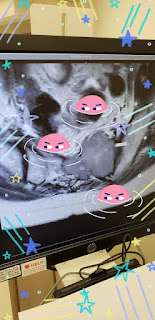

But later on that evening, I decided to do as my Drs and Nurses always say:.... "Go To ER! or Urgent Care! if you have Pain, Fever, etc... So I went, as the pain in my lower back, hips, pelvic area is erratically painful, with different type of pains all the time. So I thought it best to get an updated xray, as I've had a few crazy "slip, trip, ALMOST falls. Ever since my July fractured RIB, I've realized 9 years of crazy Ouchies, may have been other fractures, sprains, bruises, bone involved issues, that I ignored. So I went, was seen by a wonderful, thorough Dr, and the good news is... no new fractures, just all my myeloma plasmacytoma tumors, lytic lesions, etc affecting my nerves, muscles, etc.... Hmmmm ya think I should do the Radiation??? I think I should, as better to be ProActive, than ReActive, right!! And when that pain comes.... OMG... it's truly unbearable... especially since it's at night, when I've stopped moving around... Crazy stuff!